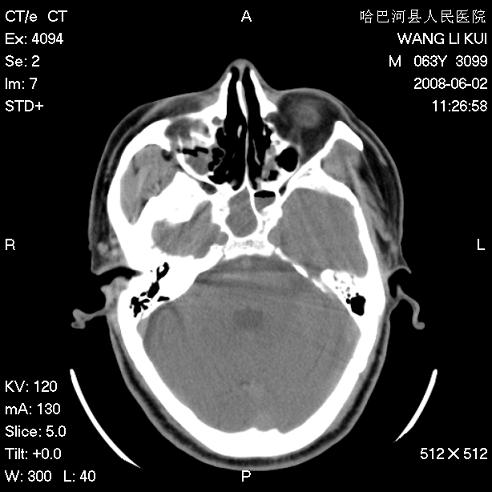

标题: CT13803:反复性鼻塞、流涕一年余 [打印本页]

标题: CT13803:反复性鼻塞、流涕一年余

副鼻窦炎,右上额窦积脓。左眼肌锥内见致密影,视神經受压

全组副鼻窦炎 肌锥内高密度灶。建议进一步检察检查

1、全组副鼻窦炎。

2、左眼眶肌锥内病变,小血管瘤?建议增强。

1)全副鼻窦炎(左侧上颌窦黏膜下囊肿或息肉)。2)左眼眶肌锥内不规则小结节状软组织密度影;考虑为小血管瘤可能。建议行ct增强扫描检查。

全组副鼻窦炎,左侧肌锥内不规则形软组织肿块影,与眼外肌密度相当,左侧视神经受压,肿块与视神经及眼外肌分界清晰,眼外肌无增粗,眶壁无破坏,球后脂肪间隙不模糊,考虑良性改变,小血管瘤或神经源性肿瘤可能,建议增强扫描。

谢谢,增强扫描做了,眶内病灶与海绵窦同步明显强化,血管瘤